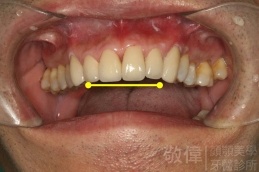

| 6 | 前牙美容 | 矯正+牙齦增補+晶鑽全瓷冠 | ||

| 7 | 前牙美容 | 矯正+晶鑽全瓷冠 | ||